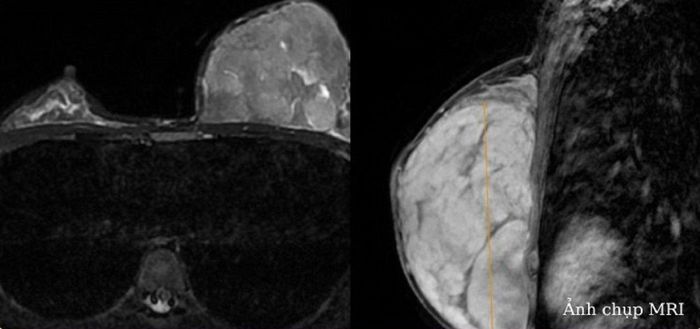

Quá trình siêu âm vú, bác sĩ nhận thấy hình ảnh tăng âm, tăng kích thước tuyến vú trái. Chụp MRI tuyến vú thấy khối u lớn nhu mô vú trái, không xân lấn thành ngực, kích thước 124x87x64 mm.